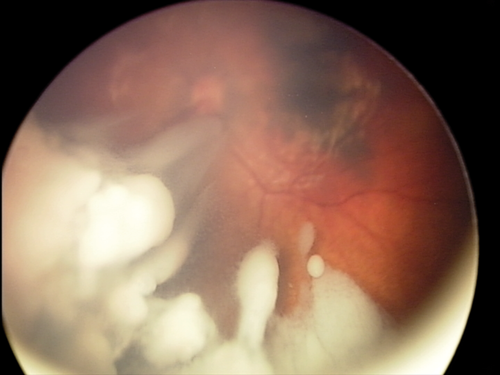

The long held principle of avoiding entering the eye was challenged with the introduction of this new treatment in 2009, and has been a paradigm shift in management. Vitreous disease is less responsive to all other forms of treatment, and has been a major cause of failure in the past. IVC involves pars-plana injection of one or two chemotherapeutic agents (typically melphalan, topotecan, or carboplatin) directly into the vitreous, after anterior chamber paracentesis, with cryotherapy to the injection site. This highly effective treatment is inexpensive, and does not require a specialised set-up. It can therefore be offered in most retinoblastoma centres in developing countries, which has reduced enucleation rates markedly in recent years (Figure 2).

Figure 2. Successful treatment of extensive vitreous disease with intravitreal chemotherapy.